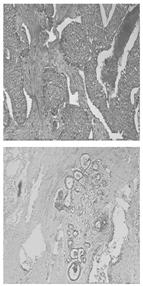

Table 11 presents a comparison between the mask images generated using three different frameworks and the ground truth masks for image segmentation. In Table 12, the performance comparison of various models on the BUSI and BreastDM datasets is presented, emphasizing their respective performance metrics. The methods for calculating performance metrics are detailed in Appendix A.

Table 11.

Comparison of different models using datasets.

For the BUSI dataset, the U-KAN model demonstrates superior performance across most metrics relative to U-Net and U-Net++. Specifically, U-KAN achieves the highest accuracy (0.933), precision (0.754), and F1 score (0.747). Additionally, it records the highest specificity (0.963) and AUC (0.935), although its recall (0.740) is marginally lower than that of U-Net++ (0.749). These results indicate that U-KAN offers balanced and robust performance, excelling particularly in accuracy and specificity, which are critical for reliable image segmentation.

Regarding the BreastDM dataset, all three models exhibit high accuracy, yet U-KAN again shows the best overall performance. U-KAN achieves the highest accuracy (0.986), recall (0.870), F1 score (0.728), specificity (0.993), and AUC (0.838). In comparison, U-Net++ demonstrates slightly lower performance with an accuracy of 0.985 and an AUC of 0.822, while U-Net exhibits an accuracy of 0.983 and an AUC of 0.815.

These findings suggest that U-KAN is particularly effective for image segmentation tasks, especially in the context of early breast cancer diagnosis. It provides superior accuracy, specificity, and balanced performance across other metrics compared to U-Net and U-Net++, thus offering enhanced capabilities for detecting early-stage breast cancer lesions. Consequently, U-KAN’s advanced performance metrics underscore its potential as a reliable model for clinical applications in breast cancer detection.